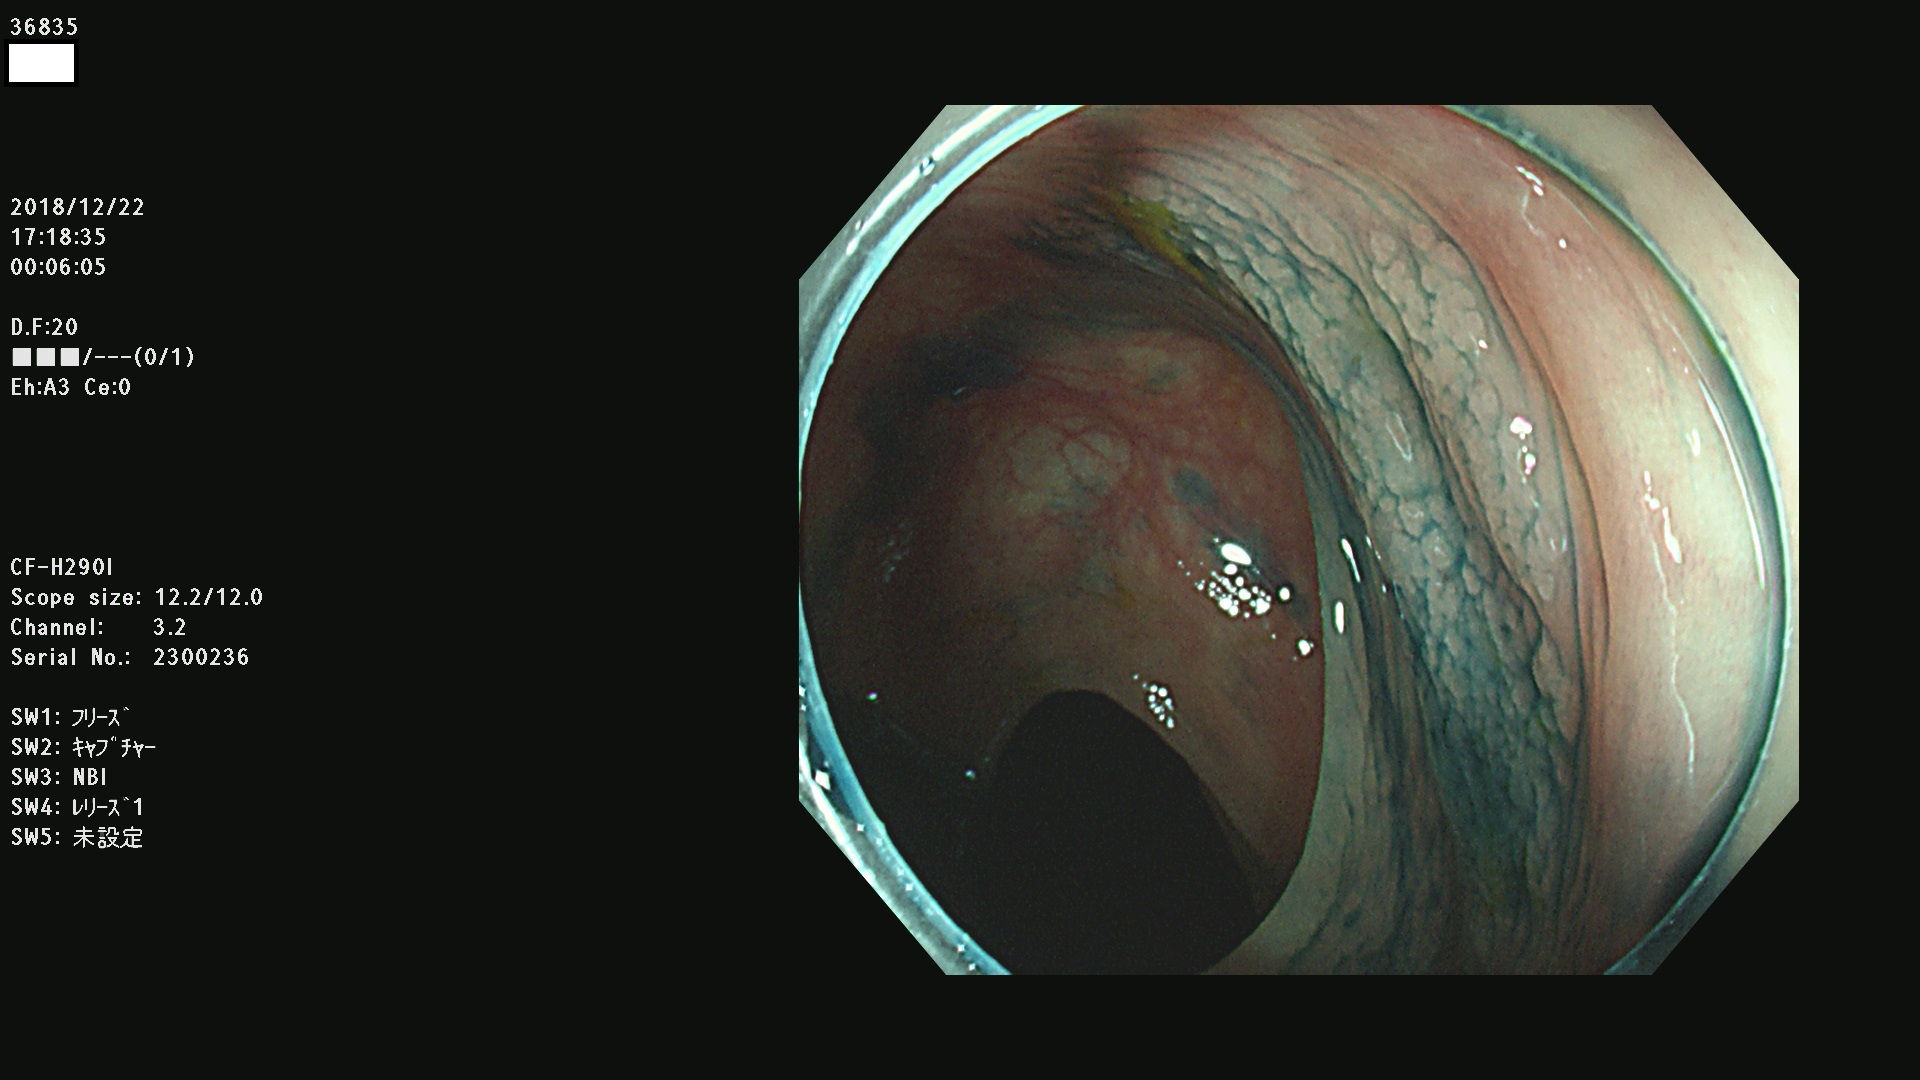

発見困難で危険性の高い平坦型病変(上記100名より抽出)

36804 36806 36807 36808 36809 36810 36811 36813 36815 36816 36817 36818 36820 36821 36822 36824 36825 36826 36828 36829 36830 36831 36832 36833 36834 36835 36837 36840 36841 36842 36845 36846 36848 36849 36851 36852 36853 36854 36855 36857 36859 36860 36861 36862(SSAPのみ) 36863 36864 36866 36868 36869 36870 36873 36875 36877 36878 36879 36881 36882 36883 36884 36885 36886 36887 36888 36889 36891 36892 36893 36894 36895 36896 36897 36898 36899